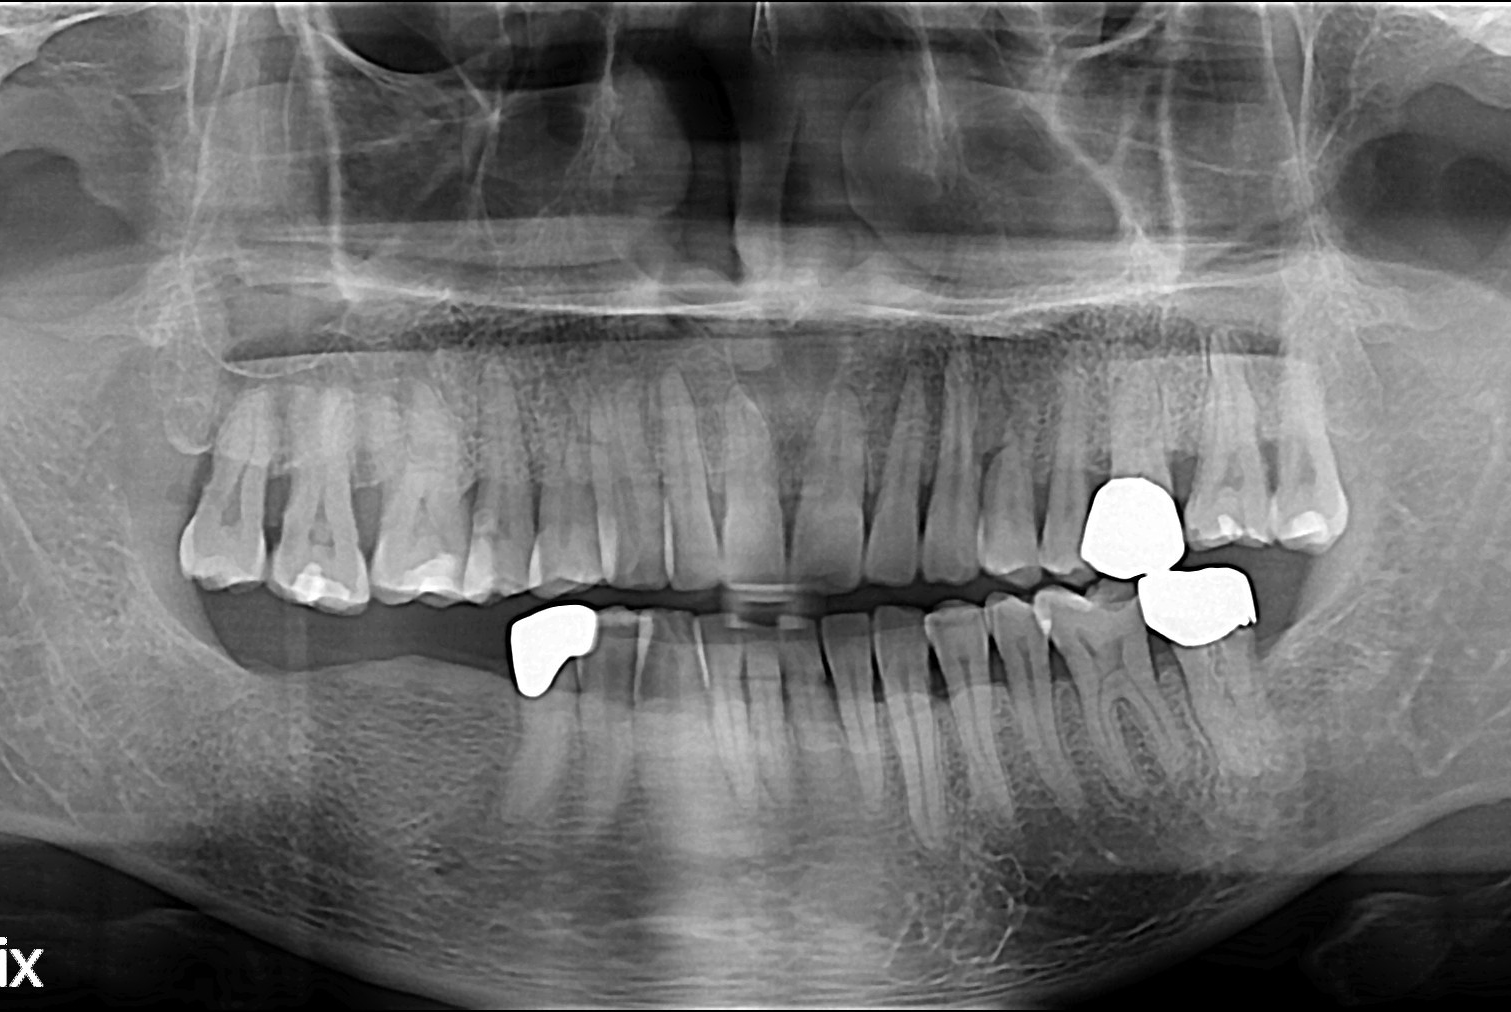

[임플란트] 임플란트

치료전 : 2019-05-10

세종치과는 많은 환자와 다양한 케이스를 바탕으로 항상 편안한 임플란트 수술을 제공하고자 노력하고,

오래동안 튼튼히 쓸 수 있는 임플란트 수술을 가장 큰 목표로 삼고 있습니다